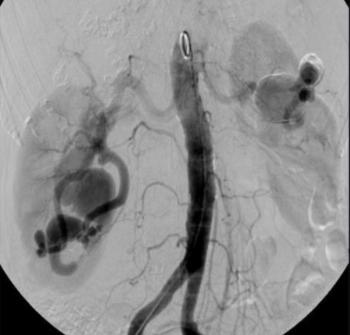

MAV Renale

Général

Rendu-Osler++

Embolisation par Coil ++